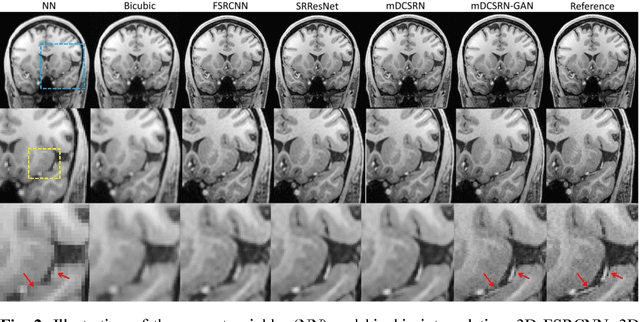

Abstract:High-resolution (HR) magnetic resonance imaging (MRI) provides detailed anatomical information that is critical for diagnosis in the clinical application. However, HR MRI typically comes at the cost of long scan time, small spatial coverage, and low signal-to-noise ratio (SNR). Recent studies showed that with a deep convolutional neural network (CNN), HR generic images could be recovered from low-resolution (LR) inputs via single image super-resolution (SISR) approaches. Additionally, previous works have shown that a deep 3D CNN can generate high-quality SR MRIs by using learned image priors. However, 3D CNN with deep structures, have a large number of parameters and are computationally expensive. In this paper, we propose a novel 3D CNN architecture, namely a multi-level densely connected super-resolution network (mDCSRN), which is light-weight, fast and accurate. We also show that with the generative adversarial network (GAN)-guided training, the mDCSRN-GAN provides appealing sharp SR images with rich texture details that are highly comparable with the referenced HR images. Our results from experiments on a large public dataset with 1,113 subjects showed that this new architecture outperformed other popular deep learning methods in recovering 4x resolution-downgraded images in both quality and speed.

Abstract:High-resolution (HR) magnetic resonance images (MRI) provide detailed anatomical information important for clinical application and quantitative image analysis. However, HR MRI conventionally comes at the cost of longer scan time, smaller spatial coverage, and lower signal-to-noise ratio (SNR). Recent studies have shown that single image super-resolution (SISR), a technique to recover HR details from one single low-resolution (LR) input image, could provide high-quality image details with the help of advanced deep convolutional neural networks (CNN). However, deep neural networks consume memory heavily and run slowly, especially in 3D settings. In this paper, we propose a novel 3D neural network design, namely a multi-level densely connected super-resolution network (mDCSRN) with generative adversarial network (GAN)-guided training. The mDCSRN quickly trains and inferences and the GAN promotes realistic output hardly distinguishable from original HR images. Our results from experiments on a dataset with 1,113 subjects show that our new architecture beats other popular deep learning methods in recovering 4x resolution-downgraded im-ages and runs 6x faster.

Abstract:Magnetic resonance image (MRI) in high spatial resolution provides detailed anatomical information and is often necessary for accurate quantitative analysis. However, high spatial resolution typically comes at the expense of longer scan time, less spatial coverage, and lower signal to noise ratio (SNR). Single Image Super-Resolution (SISR), a technique aimed to restore high-resolution (HR) details from one single low-resolution (LR) input image, has been improved dramatically by recent breakthroughs in deep learning. In this paper, we introduce a new neural network architecture, 3D Densely Connected Super-Resolution Networks (DCSRN) to restore HR features of structural brain MR images. Through experiments on a dataset with 1,113 subjects, we demonstrate that our network outperforms bicubic interpolation as well as other deep learning methods in restoring 4x resolution-reduced images.